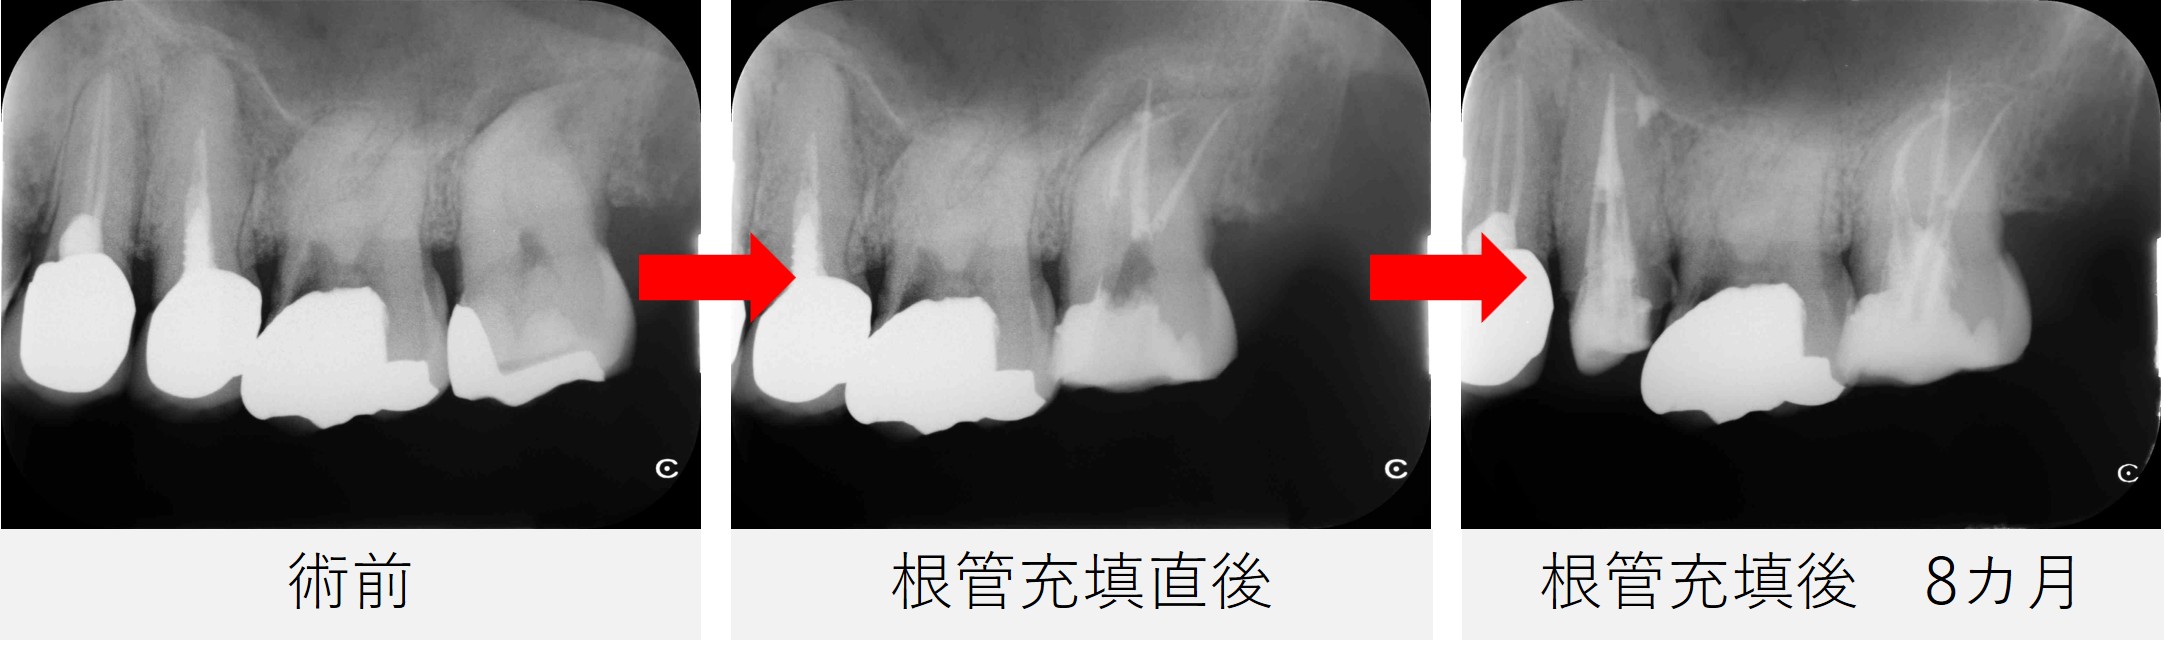

- 根管充填を行い、仮封しました。

レントゲン撮影で、根管充填の状態が良好であることを確認しました。

根管充填後は、画像と症状の両面から経過を確認していきました。

根管充填後から8カ月

- 痛みはなく、鼻の症状も認められませんでした。

- レントゲンおよびCT撮影を行い、根尖部の黒い影が縮小し、骨の回復傾向が確認されました。

- 炎症の改善が見られたため、最終補綴(被せ物の作製)へ移行する予定としました。

今回の症例では、強く湾曲した根管と、上顎洞にまで及んだ炎症という難しい状況でしたが、

丁寧な根管治療によって炎症が改善し、歯を残すことができました。